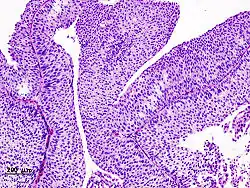

Urothelkarzinom der Harnblase

Lichtmikroskopisches Präparat, gefärbt mit HE

Mehr als 90 % der Urothelkarzinome befinden sich in der Harnblase. Wie die Papillome sind sie vor allem an der Blasenrückwand oder der Blasenseitenwand lokalisiert. Zudem wachsen die meisten Tumoren papillär. Dringt der Tumor in die Lamina propria ein, so spricht man von einem invasiven infiltrierenden Urothelkarzinom.[6]